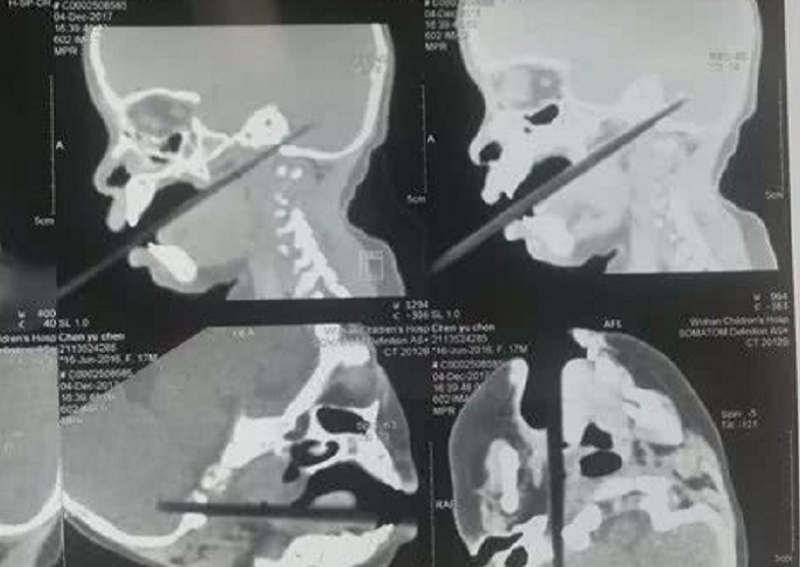

Saat bayi tersebut kehilangan keseimbangan, ia terjatuh dan sebatang sumpit tertancap di mulutnya hingga tembus ke bagian otak. Orang tua bayi yang berada di dekatnya langsung histeris saat melihat kondisi putri kecilnya. Pihak keluarga langsung bergegas ke rumah sakit untuk mendapat penanganan medis. Setidanya di rumah sakit, tim dokter langsung melakukan CT Scan pada bayi tersebut.

Tim dokter menemukan bagian sumpit sepanjang 2 centimeter telah menusuk cerebellum, atau bagian dari otak yang berfungsi mengatur gerak motorik. Sumpit juga menembus bagian vena jugularis internal. Yang lebih buruk lagi, tim dokter menemukan adanya butiran beras di sumpit tersebut.

Namun, untungnya sumpit tersebut tak sampai menembus bagian penting dari otaknya. Tim dokter segera melakukan operasi dan berjalan sukses. Saat ini putri kecil itu masih dalam proses perawatan intensif pihak rumah sakit dan menghadapi risiko infeksi intrakranial. Dokter mengingatkan para orang tua untuk tidak membiarkan anak-anak berjalan dengan membawa sumpit dari besi ataupun bambu.